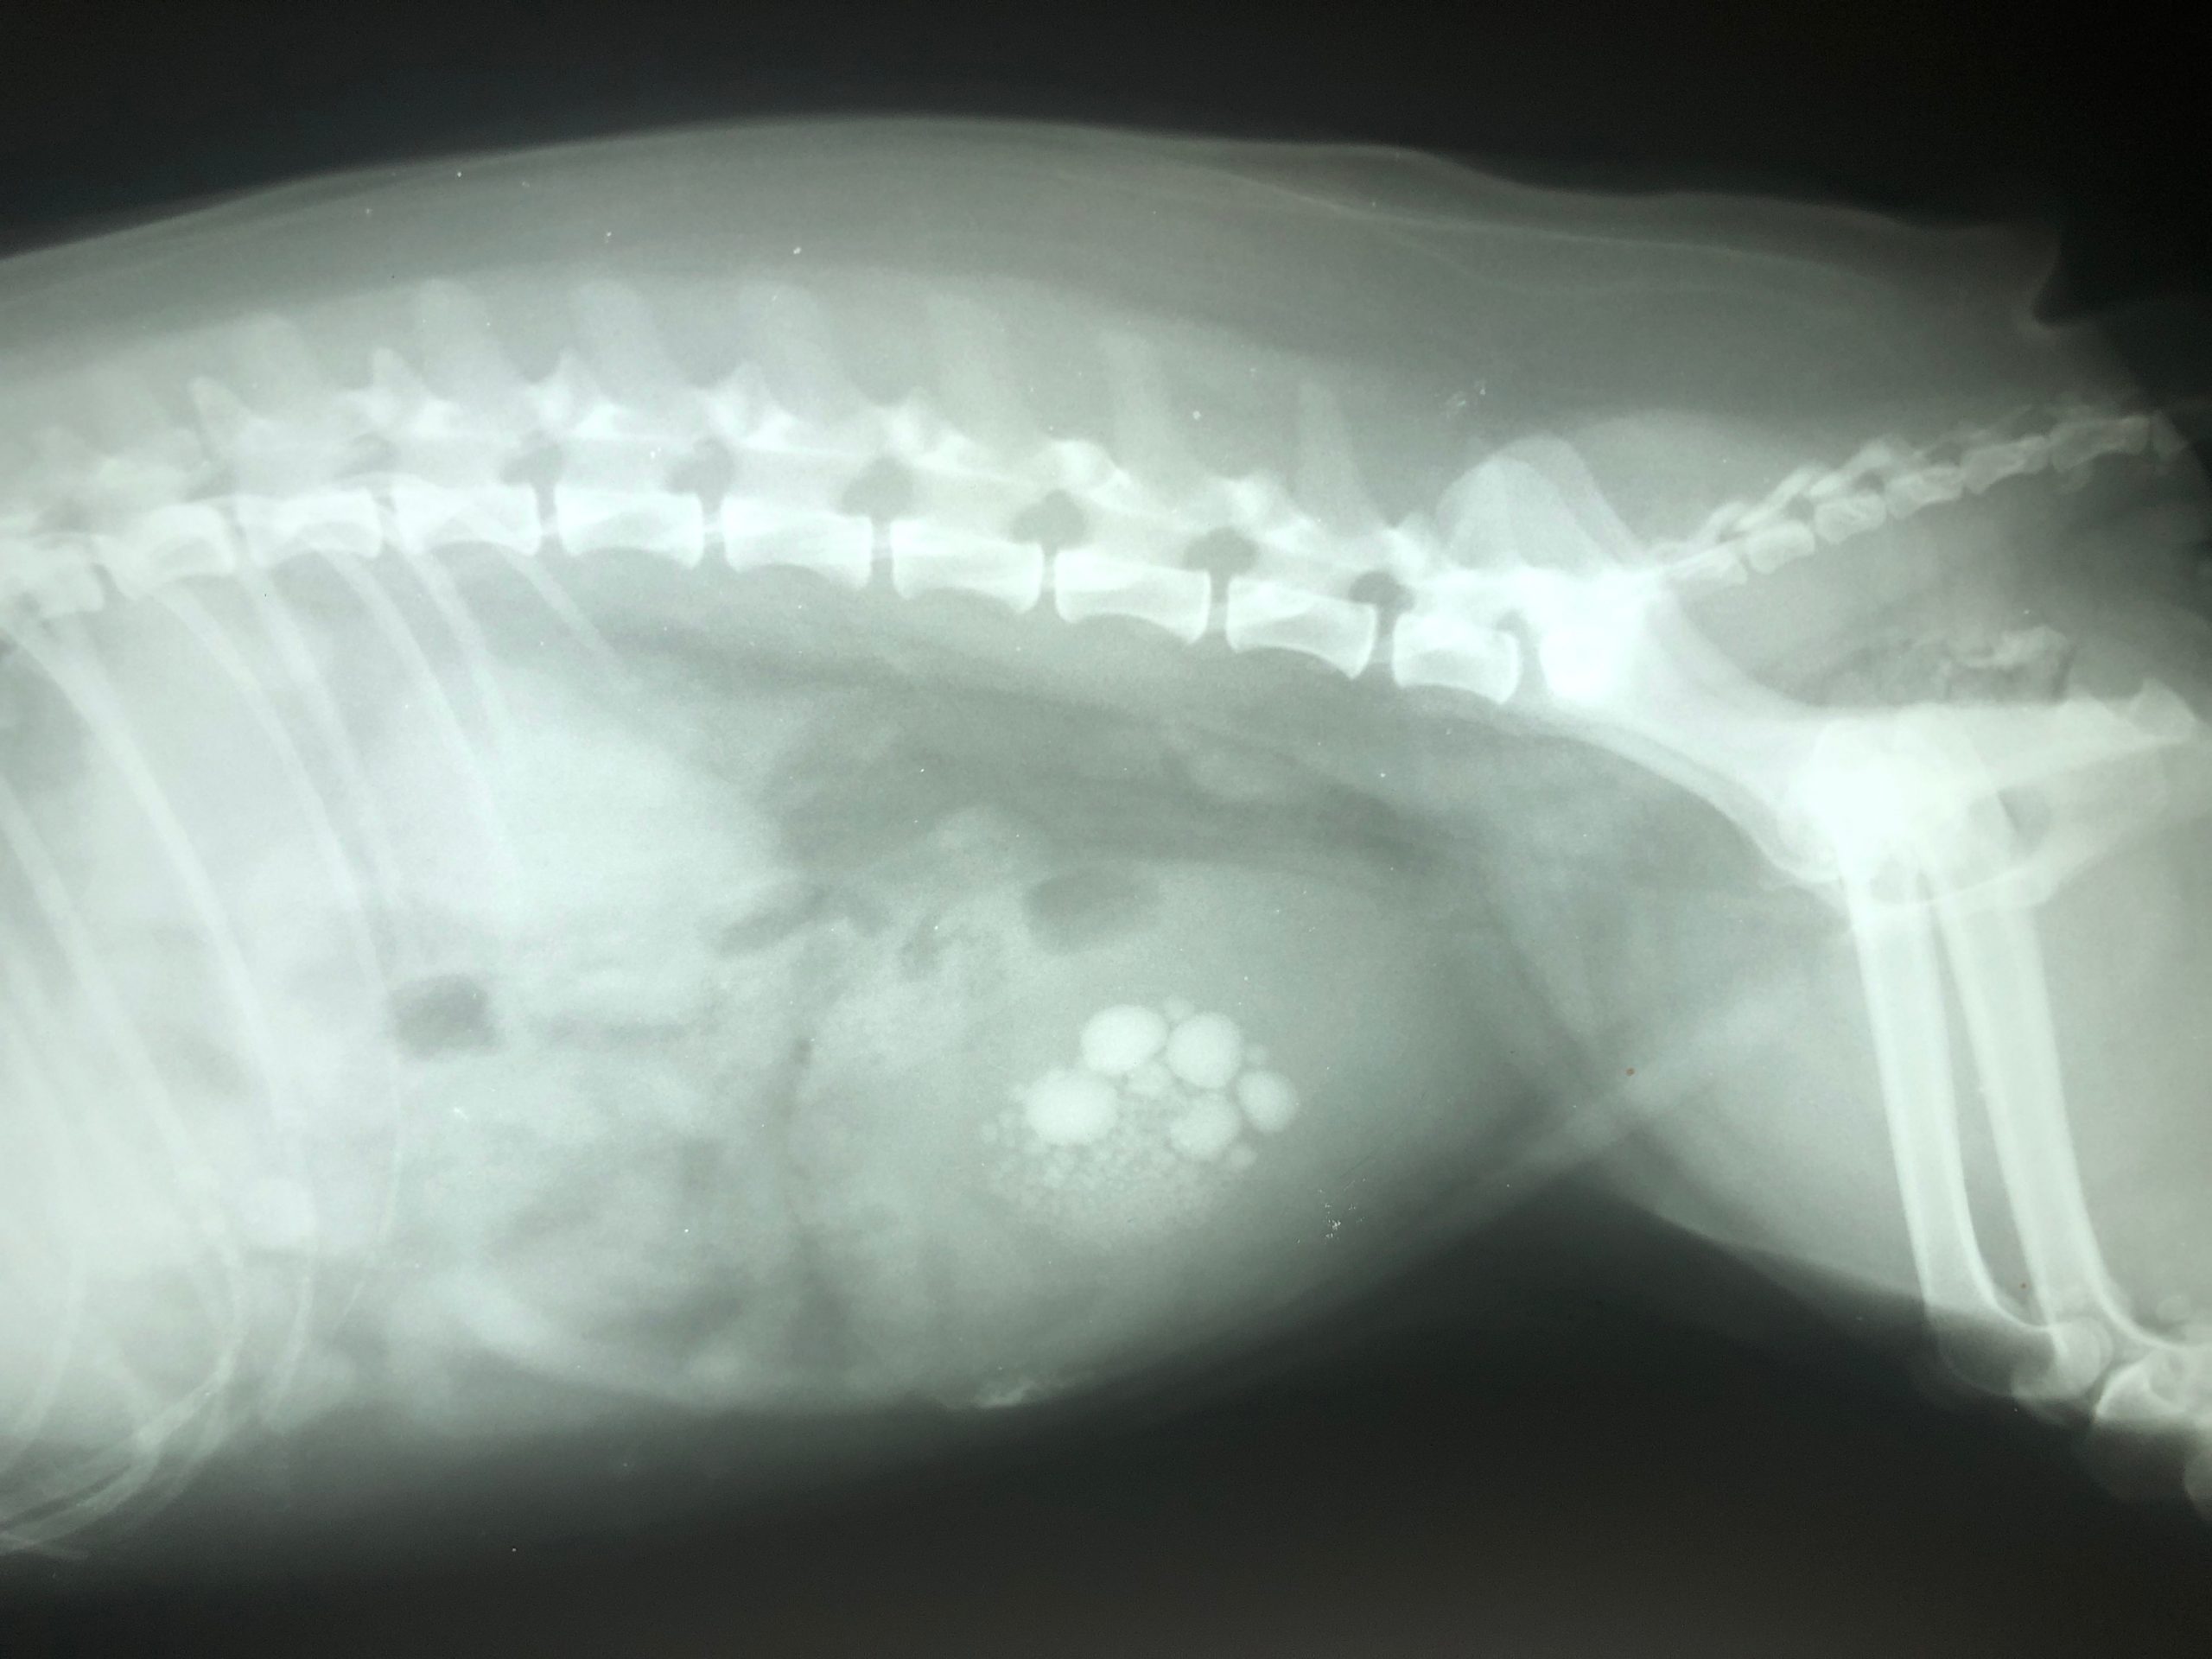

Urolithiase - Lagere UrinewegenUrolithiase komt vaak voor bij honden en katten. De urolithen kunnen zich bevinden in de bovenste (nieren en ureters) of lagere urinewegen (blaas en urethra)…